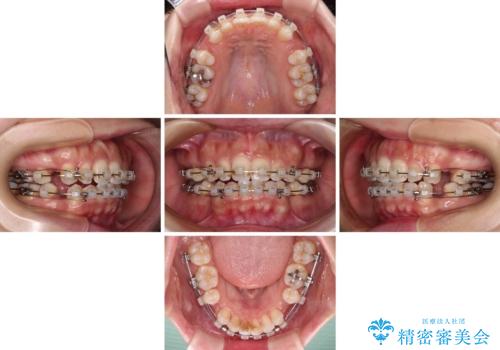

唇が閉じにくい ワイヤー装置での抜歯矯正

レントゲン写真での分析結果からは、抜歯矯正をするかどうか悩む境界線上でしたが、主訴が口元の突出感であったため、上下左右の第一小臼歯4本を抜歯して矯正治療を行うこととしました。

上下ともに前歯が少し舌側に傾斜したような仕上がりとなりましたが、口が閉じやすくなったとのことで、患者様には大変満足していただけました。